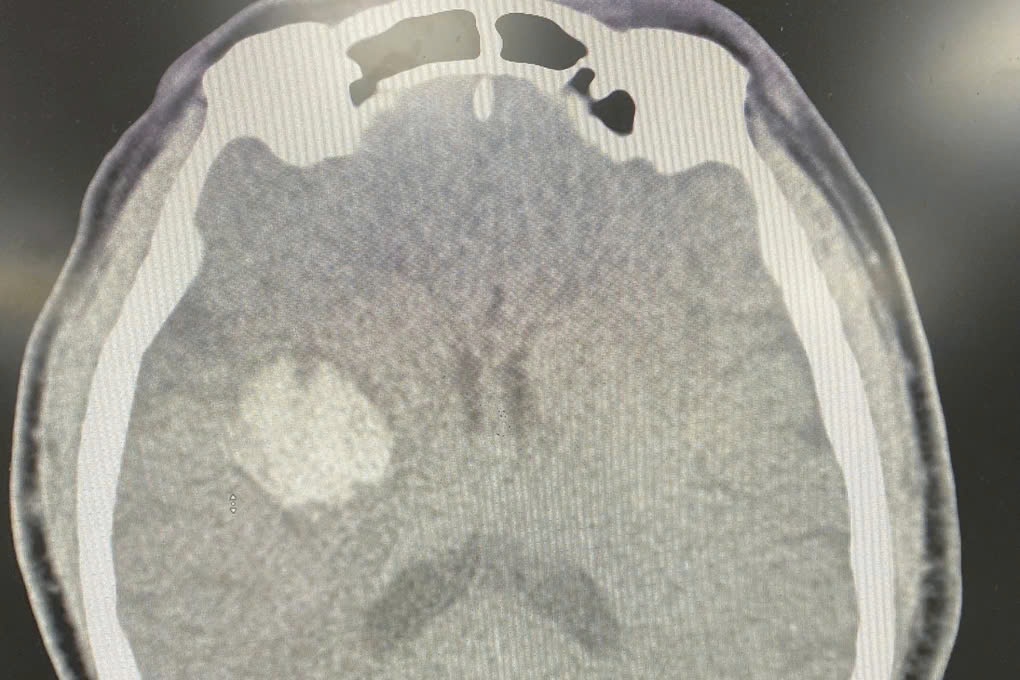

BS Phạm Duy Hoàng, Khoa Cấp cứu cho biết, kết quả chụp cắt lớp vi tính sọ não dựng hình mạch máu não (CTA) cho thấy  hình ảnh xuất huyết não vùng nhân xám trung ương phải, không có bất thường mạch máu não.

Hình ảnh chụp cắt lớp vi tính cho thấy có chảy máu não